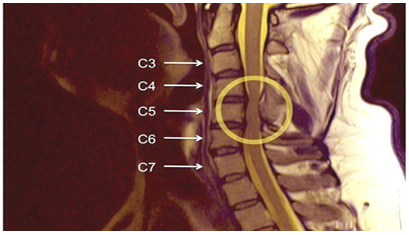

d) Isquemia da medula espinhal: A isquemia da medula espinhal provavelmente desempenha um papel no desenvolvimento do MCE. O mecanismo preciso da isquemia medular não é compreendido completamente, foi demonstrado apenas histologicamente, apresentado na figura 1 e 2.

Figura1: Mielopatia cervical espondilótica. Fonte: Canedo et al(12).

Figura 2: Localização da Mielopatia cervical espondilótica.

Fonte: Canedo et al(12)